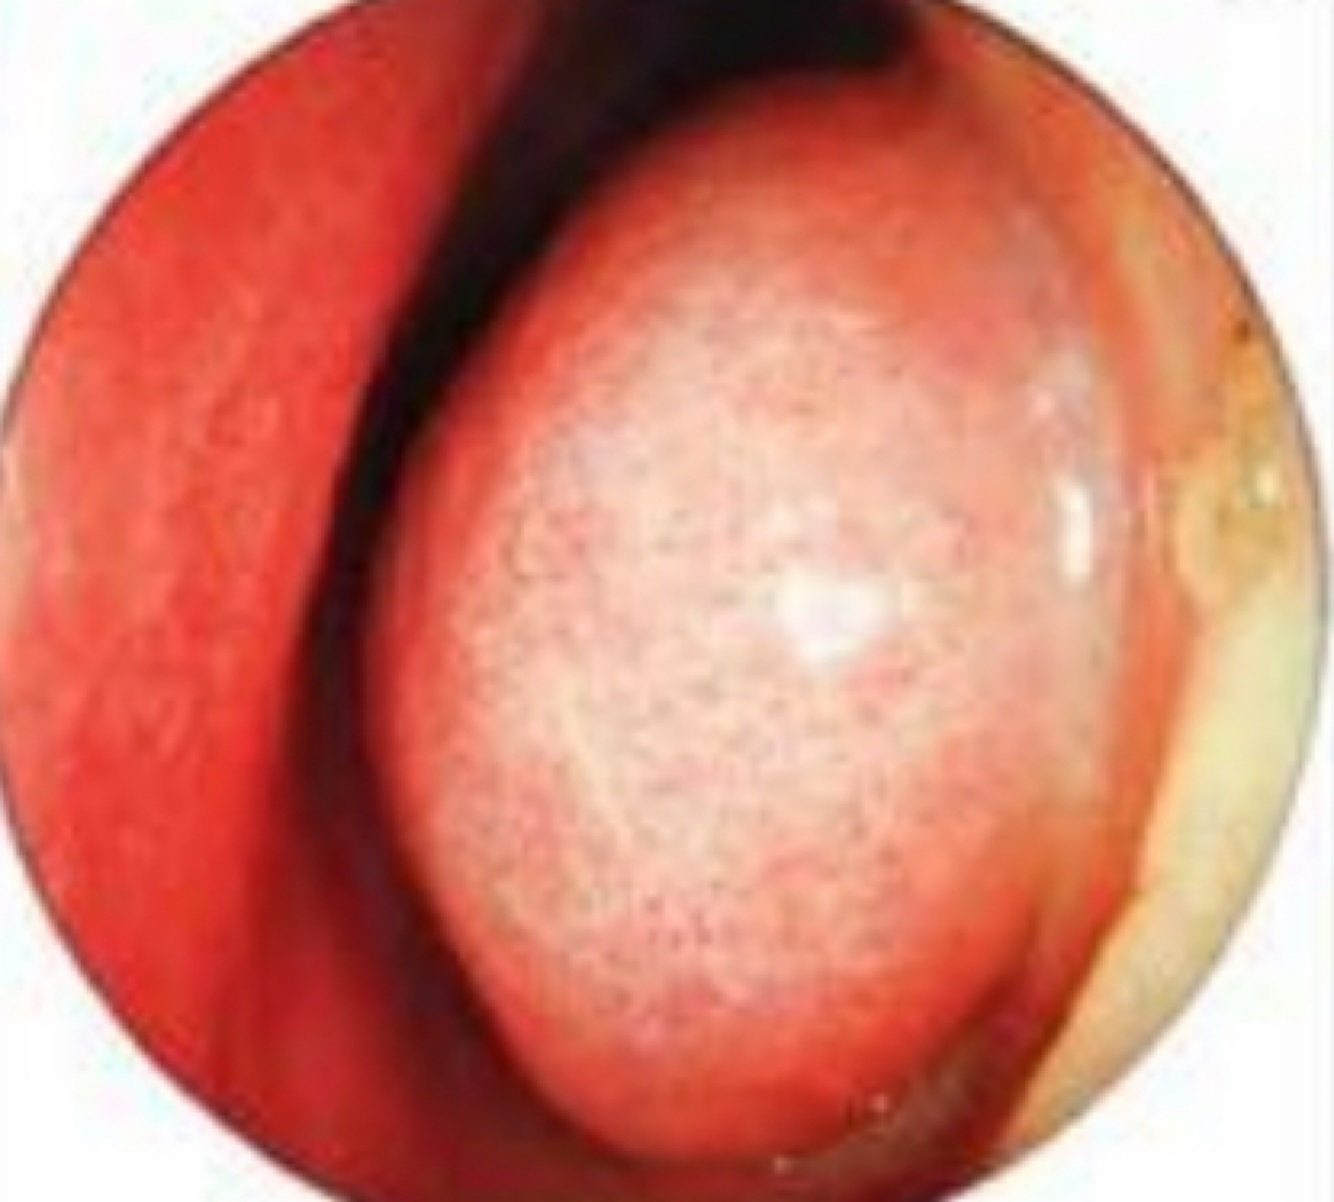

Q

¿Qué es esto?

A

Concha media bulosa